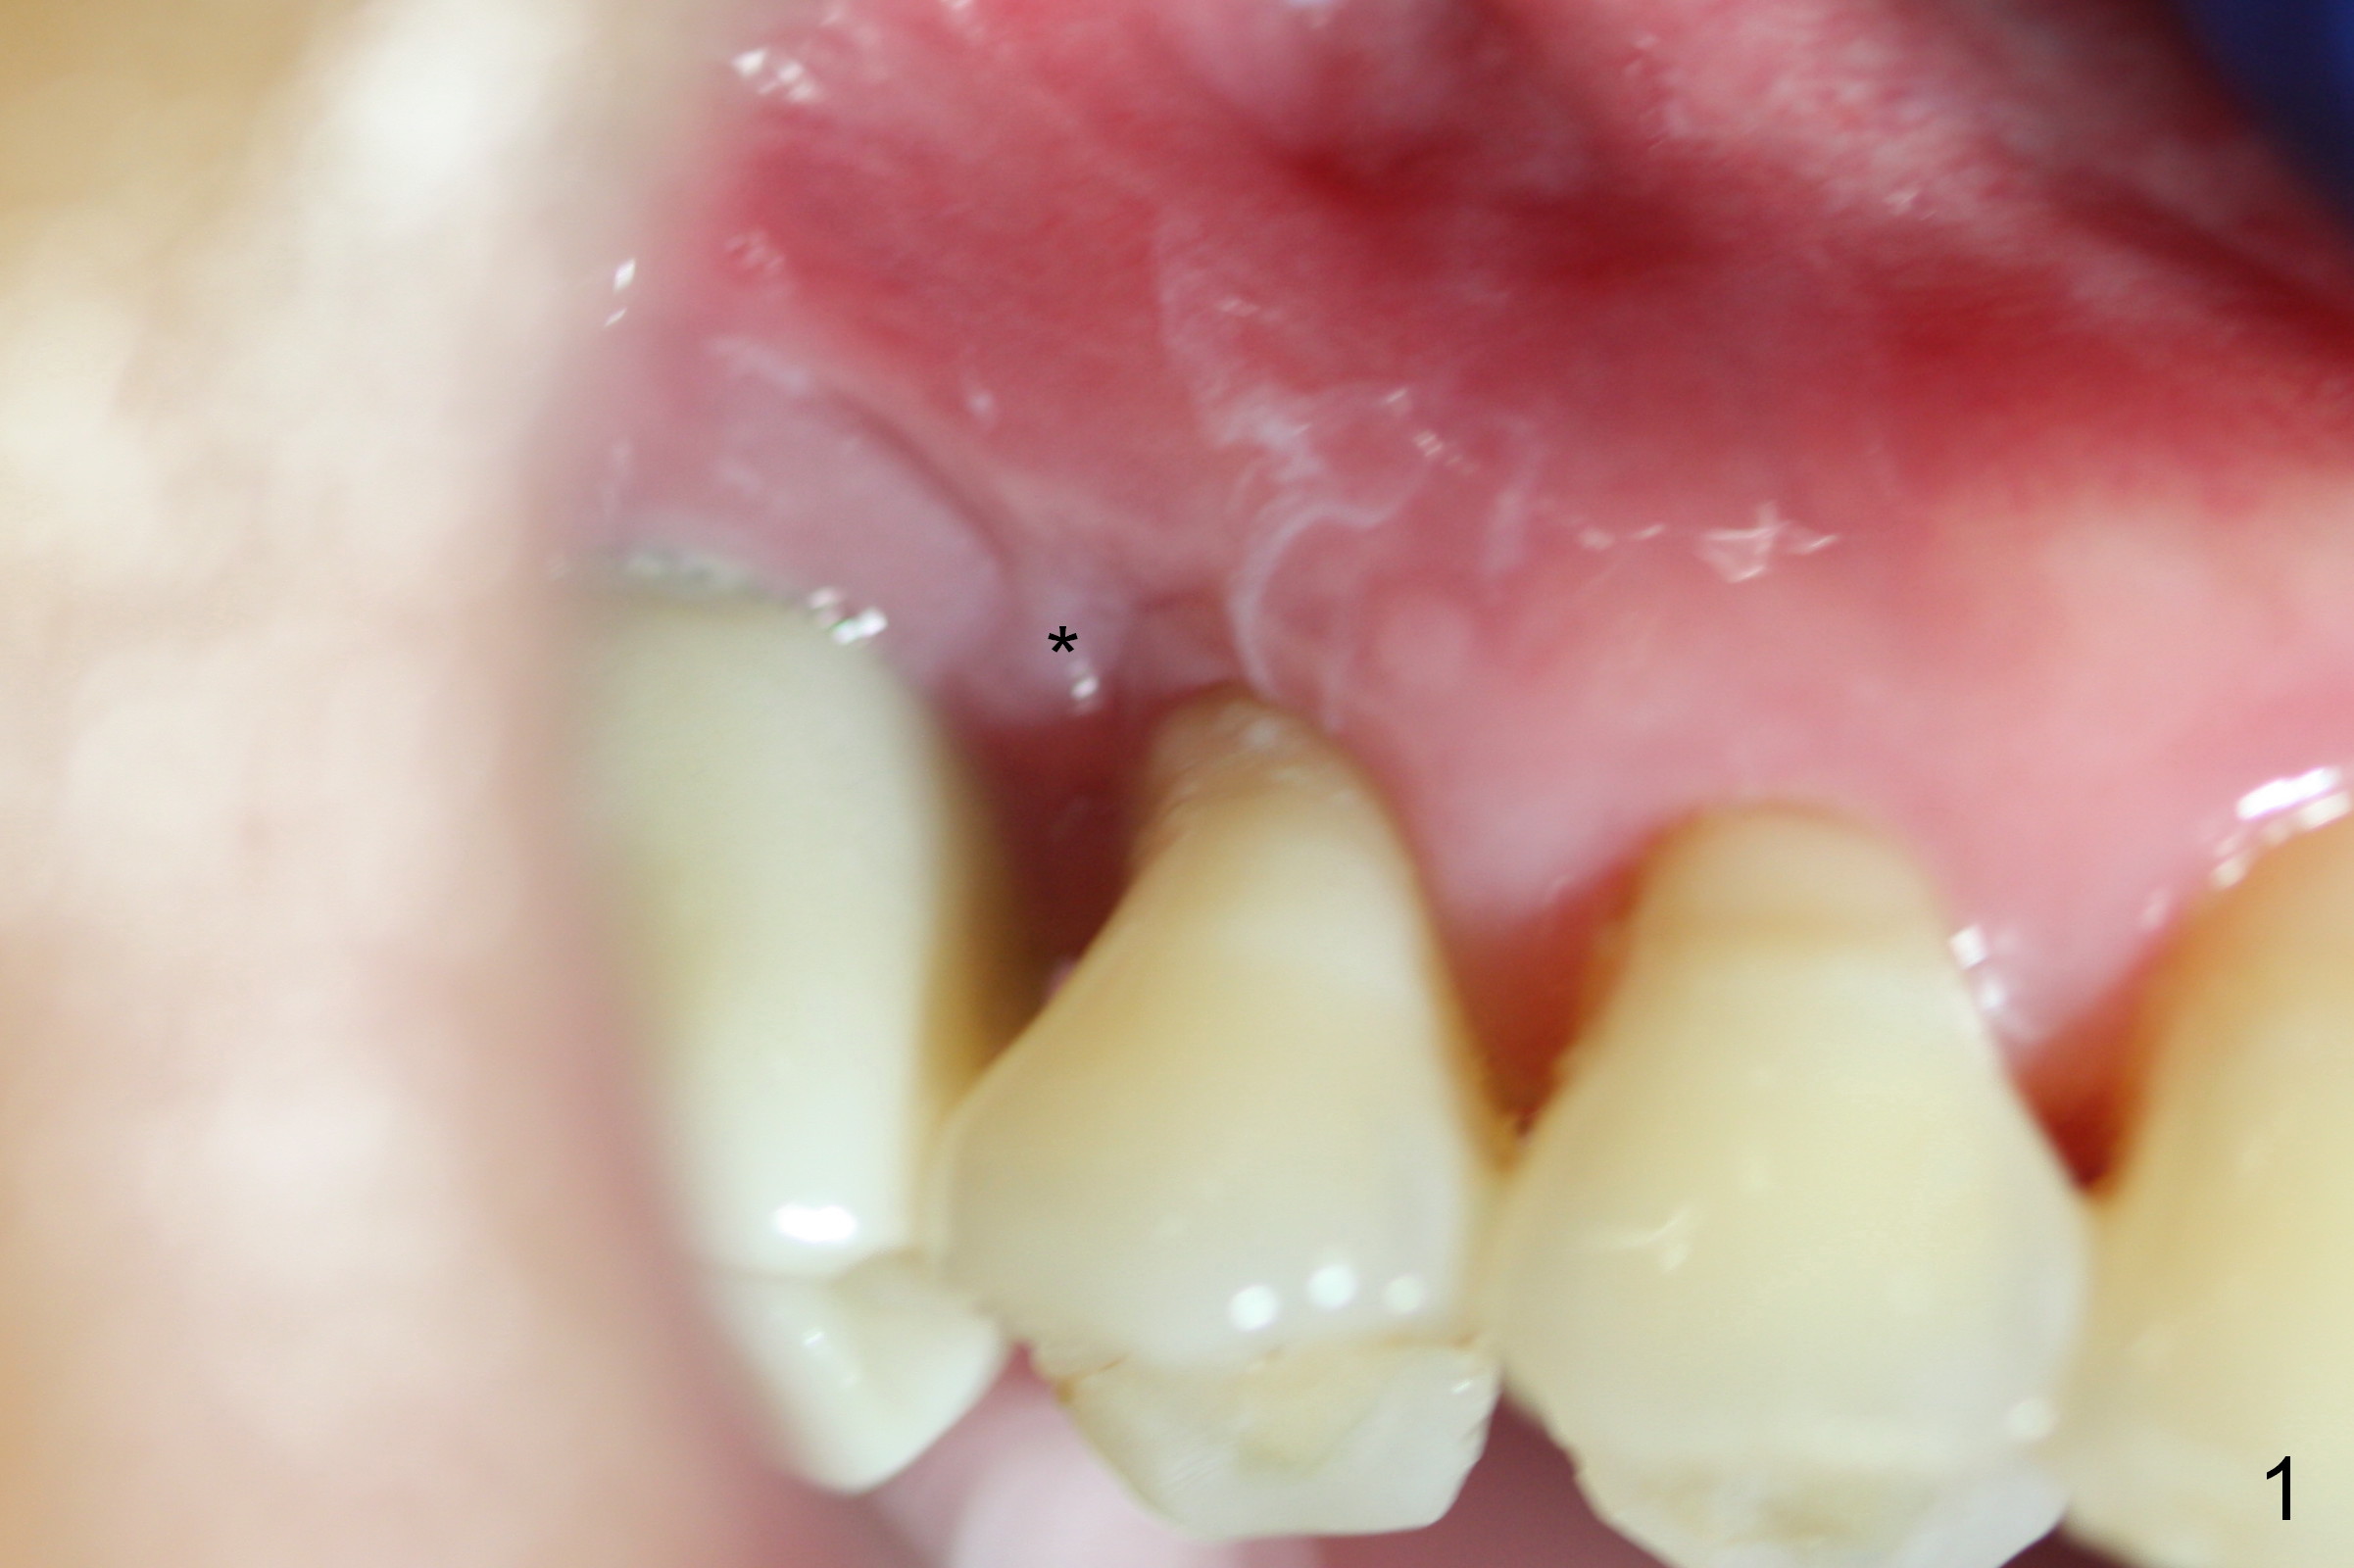

The distal buccal (Fig.1) and palatal (Fig.2) papillae (*) are recessive at the tooth #4.  Following extraction and use of 3.8 mm Magic Drill, a 4.5x13 mm implant is placed lower than the mesial crest (Fig.3) to reduce the chance of the distal implant thread exposure.  The latter is a measure to decrease peri-implantitis.  A 4.5x5.7(4) mm pair abutment is placed (Fig.4,5).  The remaining socket is filled with allograft/Osteogen placement.  The large space between #3 and 4 implants is occupied by the healthy gingiva, where bone graft cannot get in.

Six days postop, the distobuccal margin of the immediate provisional appears to be overbuilt (Fig.6 *).  The overhang was made to cover the distobuccal opening of the socket (Fig.4).  In addition to daily use of water pik, cleaning with .25% Sodium Hypochlorite contributes to the shiny surface of the provisional.  From now on, use cotton pellets soaked with the diluted bleach to clean the provisional and abutment (if exposed) every visit.  For this case, the overhang will be trimmed when the patient returns in 2 weeks so that the distal papilla may grow downward. The mesial contact should be re-established (^).